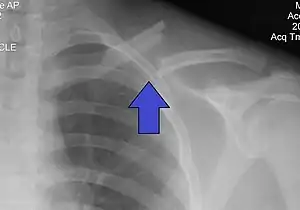

| X-ray of a left clavicle fracture | |